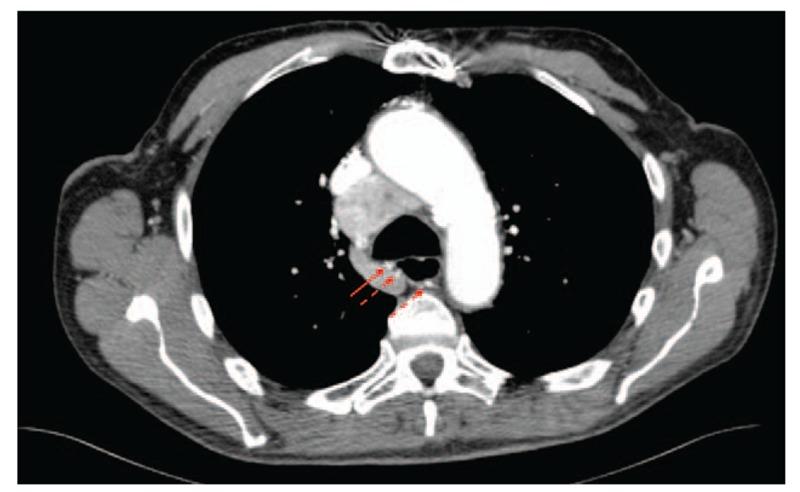

We present three episodes of massive hemoptysis in two patients, the first with comorbid Alagille syndrome including multiple cardiac and pulmonary vascular abnormalities and the second with thyroid cancer metastatic to the mediastinum.

我们报告了两名患者的三次大量咯血发作,第一名患者合并阿拉吉耶综合征,包括多种心脏和肺血管异常,第二名患者患有甲状腺癌纵隔转移。